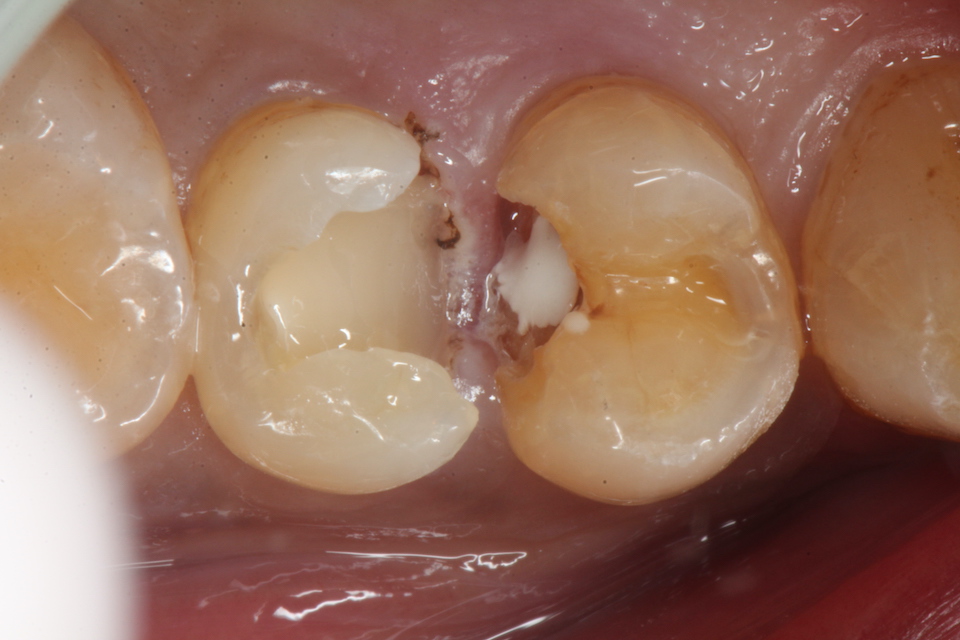

下顎7番の頬側歯茎部カリエスの原因 2025.06.04